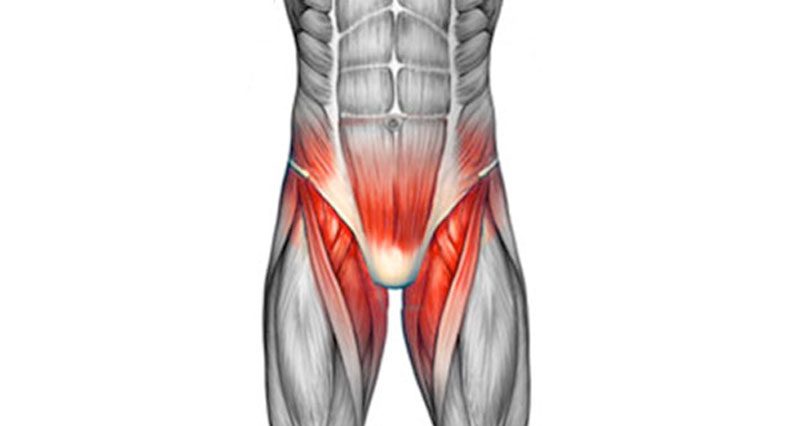

درد کشاله ران

درد کشاله ران | علتها، تشخیص و درمان درد کشاله ران یکی از مشکلات رایجی هست که هم در مردان و هم در زنان ممکنه دیده بشه. این درد میتونه بهصورت ناگهانی یا بهمرور زمان ظاهر بشه و دلایل مختلفی داشته باشه. در ادامه به زبان ساده توضیح میدیم که چرا این درد ایجاد میشه، […]